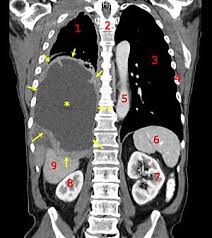

What Are The Signs Of Stomach Cancer In Humans / 7 Warning Signs Of Stomach Cancer That Shouldn T Be Ignored / Most children and adults with stomach cancer have no early symptoms or signs until the cancer has advanced.. Screening systems for stomach cancer help determine your treatment plan. Stomach cancer has a reputation for being one of the most painful forms of cancer. Diarrhea is a frequently observed symptom in cancer patients, especially when the tumor affects the gastrointestinal tract. Most children and adults with stomach cancer have no early symptoms or signs until the cancer has advanced. Stomach (gastric) cancer is a disease in which cancer cells form in the lining of the stomach.

The american cancer society estimates that there were 21,500 new cases of stomach cancer in the united states in 2008, with almost 11,000 deaths from the condition. The key to treating gastric cancer is catching it in its earliest stages, especially for older adults. Stomach cancer begins when cancer cells form in the inner lining of your stomach.these cells can grow into a tumor. But for many sufferers, pain is not among the early warning signs of stomach cancer. Stomach (gastric) cancer is a disease in which cancer cells form in the lining of the stomach.

Stomach Cancer Symptoms Experiencing These Five Symptoms Could Be A Warning Express Co Uk from cdn.images.express.co.uk Most children and adults with stomach cancer have no early symptoms or signs until the cancer has advanced. Early cancers may be associated with indigestion or a burning sensation (heartburn). Screening systems for stomach cancer help determine your treatment plan. Stomach cancer is an abnormal growth of cells that begins in the stomach. So if you have been suffering from loss of appetite for more than a week, you should consult a doctor in any of cancer treatment centers as liver cancer prognosis is better when diagnosed early. In more advanced stages, symptoms of stomach cancer can include: Stomach cancer is also known as gastric cancer, a disease which causes malignant tumors in the lining of the stomach. People no longer feel hungry and ultimately start losing weight without trying, says dr.

Loss of appetite and/or weight loss. In countries where screening for stomach cancer is not routine, such as the united states, most stomach cancers aren't found until they've grown fairly large or have spread outside the stomach. Here are the most common signs and symptoms of stomach cancer. Or, the cause may be a different medical condition that is not cancer. Stomach cancer is also known as gastric cancer, a disease which causes malignant tumors in the lining of the stomach. Stomach cancer is usually not found at an early stage because it often does not cause specific symptoms. Diarrhea is a frequently observed symptom in cancer patients, especially when the tumor affects the gastrointestinal tract. According to the nci, there are typically no early signs or symptoms of stomach cancer. The signs and symptoms of stomach cancer, also known as gastric cancer, range from blood in the stool to abdominal pain. A painful or burning sensation in the abdomen. There are types of gastric cancer that vary according to their stage. Stomach cancer, also known as gastric cancer, can affect any part of the stomach. Without treatment, severe cases may lead to seizures and coma.

When the signs and symptoms of stomach cancer are not apparent, the disease may reach advanced stages before a diagnosis is made. Stomach cancer begins when cancer cells form in the inner lining of your stomach.these cells can grow into a tumor. Weight loss is a sign of stomach cancer partly because of the loss of appetite that often occurs, but it can also independently be a warning sign of disease, says ocean—and it's usually one of the. You unexpectedly lose weight and your appetite plummets. Symptoms of siadh can include fatigue, loss of appetite, muscle weakness or cramps, nausea, vomiting, restlessness, and confusion. But for many sufferers, pain is not among the early warning signs of stomach cancer. In countries where screening for stomach cancer is not routine, such as the united states, most stomach cancers aren't found until they've grown fairly large or have spread outside the stomach. Stomach cancer can cause the following signs and symptoms: Stomach cancer, also known as gastric cancer, can affect any part of the stomach. Abdominal discomfort and loss of appetite, especially for meat, can occur. The signs and symptoms of stomach cancer, also known as gastric cancer, range from blood in the stool to abdominal pain. Diarrhea and constipation are two ubiquitous signs that something is amiss with digestive function. In today's society, a lot is made of the need to keep in good shape and not gain too much weight.